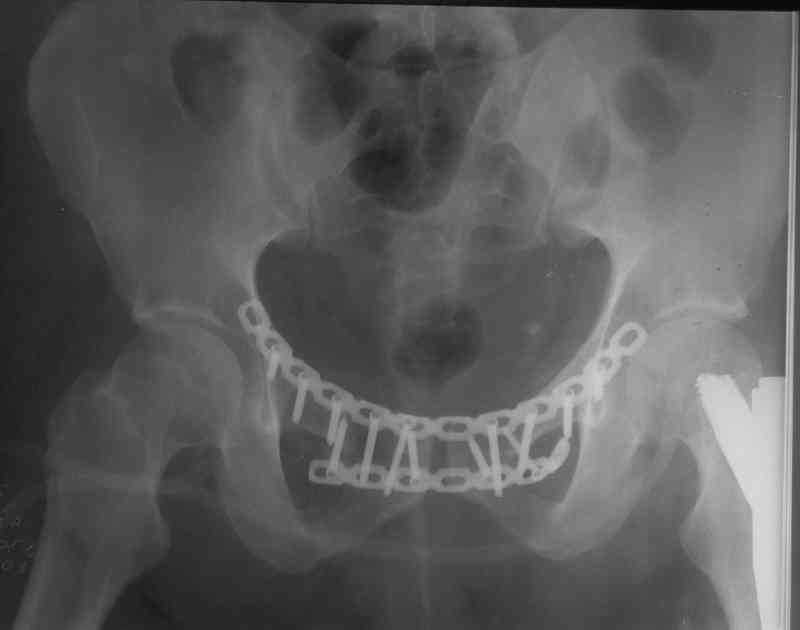

перелом бедер. Одной девушке, удачно приземлившейся с 11-го этажа, в один наркоз заштифтовали два бедра и наложили аппарат на таз окончательно, пятками и лодыжками занимались намного позже. В другом случае у 160-кг

пациента с вторично заживающей раной после лапаротомии забили гвоздь и только через три недели (после заживления лапаратомной раны) фиксировали переднее полукольцо пластинами. Это тучный пациент лечение в аппарате не перенес бы.

Пластина спереди (на лонные кости) открыто и каннюлированные винты с обеих сторон сзади - закрыто.

Предварительная репозиция может быть достигнута при помощи аппарата.